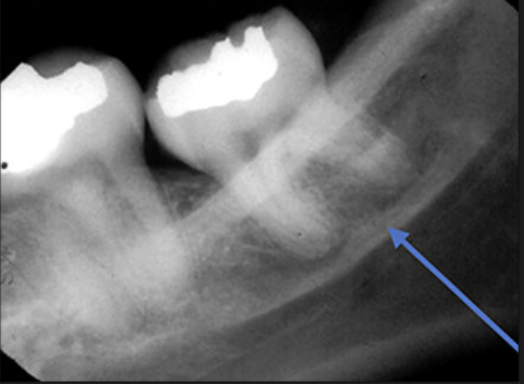

If the contacts get worse as we move back in the mouth, what radiograph error is happening?

It means we are rotated mesial-distally.

On a molar bitewing, what contacts should be open?

All contacts surrounding the 2nd molar

On a premolar bitewing, what contacts should be open?

All contacts surrounding the 2nd premolar